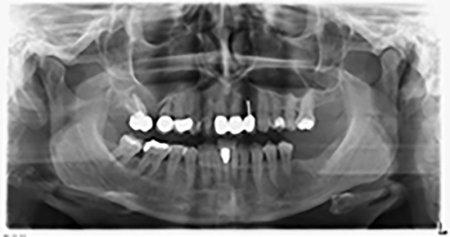

La paciente de 59 años presentaba una periodontitis avanzada, describía una desagradable sensación y un mal gusto proveniente del primer cuadrante. La evaluación clínica mostró en general marcadas profundidades de bolsa y una degeneración ósea muy avanzada en las regiones 16 y 14. El estudio radiológico corroboró estos resultados (figura 1). Las piezas dentales 16 y 14 no podían conservarse.

Imagen 1: Ortopantomografía con retirada ósea en las regiones 16 y 14*

Unos seis meses después de la extracción de las piezas 16 y 14 se realizó una tomografía digital de volúmenes (DVT, Planmeca) para realizar una planificación adecuada y reducir los riesgos al mínimo. En este punto se constató que el hueso no se había regenerado en la cantidad deseada (figuras 2 a 7).

Figuras 2 a 7: Tomografía digital de volúmenes con oferta ósea horizontal reducida.

Ortopantomografía

Imagen 20: Ortopantomografía después del tratamiento

Se colocaron implantes Sky de la empresa Bredent: pieza 16: 5,5 x 10 mm y pieza 14 4,0 x 10 mm.